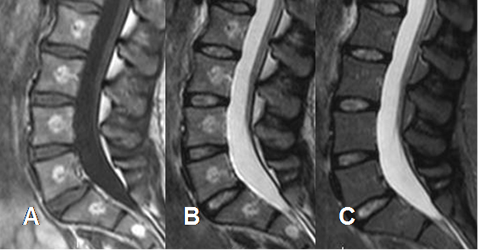

Fig 154. Hemangiomas sintomáticos.

A: RM sagital en T1, B: RM sagital en T2 y C: RM sagital en STIR. Hemangiomas vertebrales hiperintensos en T1 y T2, que no suprimen en STIR, por componente inflamatorio asociado.